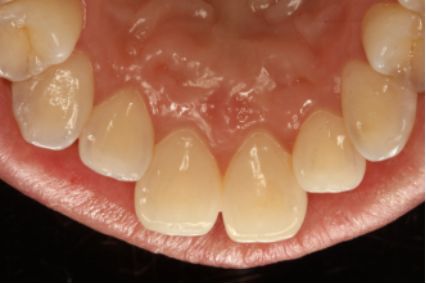

采用PT5牙周治疗仪进行全口超声龈上洁治术、超声龈下刮治术。术后5周复查可见牙龈炎症明显减轻,仍有轻度炎症,复查发现患者口腔卫生维护欠佳,再次进行口腔卫生宣教。

超声洁刮治术即刻